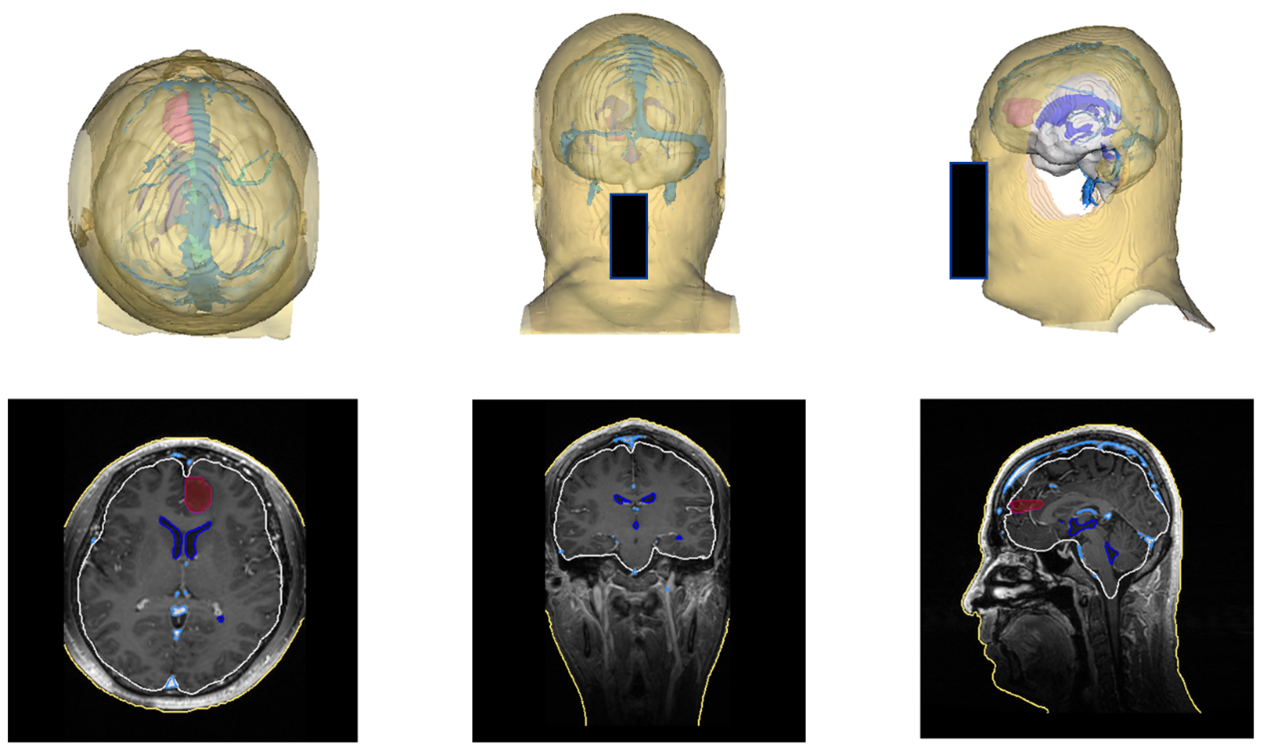

术前,基于AI和影像技术,该手术导航系统能够将磁共振、CT等影像自动进行分割重建及三维可视化处理,通过腾讯AI Lab的算法能力,一键生成定制化的3D“透明脑”,方便医生制定手术计划,向病人和家属讲解手术方案。

(术前“透明脑”生成)

借助深度相机,综合深度学习和视觉算法,该系统能实现虚拟空间和现实空间的高精度一键配准,将生成的3D“透明脑”1:1与病人实际情况进行匹配, 进行术中导航。

(术中导航)

试验数据显示,其配准精度可达亚毫米级。算法能力的提升,可将传统手术导航的配准时间由传统的近半个小时,缩短至几秒钟,为病人抢占宝贵的治疗时机。